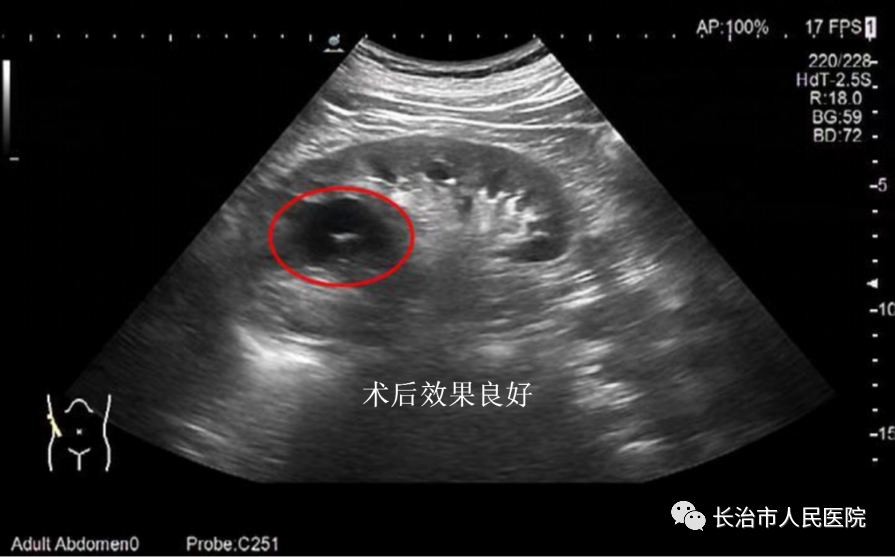

近年来,超声医学技术发展迅猛,尤其是介入超声的发展,迎来了超声从诊断到治疗的里程碑。介入超声以其针过无痕、精准微创等优势获得了临床及患者的认可。10cm大小的肝囊肿,16cm大小的肾囊肿,3cm大小的甲状腺良性结节,0.8cm大小的甲状腺恶性结节,无论其大小良恶,在崔教授精湛的操作技术下,在一根细针的舞动下,在“超声造影”等超声利器的助攻下,短短几分钟或十几分钟,病灶就被“解决”,患者体表只留下一个几乎看不到的针眼。一个巨大肾囊肿患者,术后当场在我院日间手术室门口蹦跳了几下,眉开眼笑,说感觉身体瞬间轻盈了许多。